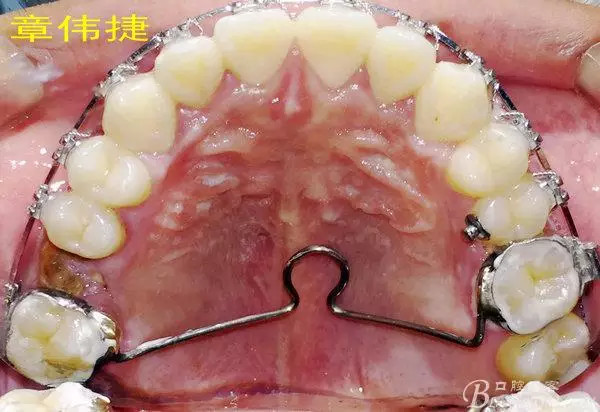

矯治八個(gè)月術(shù)中資料:

經(jīng)過8個(gè)月的治療,患者的間隙已完全關(guān)閉,患者非常滿意,后期進(jìn)入精細(xì)調(diào)整階段,建議做舌體修整術(shù),防止復(fù)發(fā)。